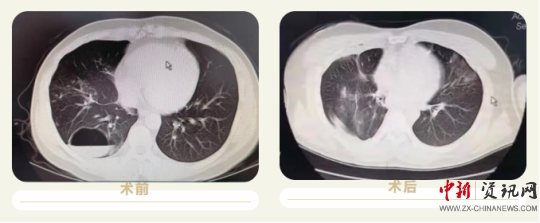

患者董某,男,32歲,因“咳嗽、咳痰伴咯血2天”收入院,患者及家屬敘述于本次入院兩天前受涼后出現(xiàn)咳嗽,咳白色粘液,有咯血,主要為痰中帶血,呈鮮血,量較少,活動后氣促,來上蔡縣人民醫(yī)院治療,經ct檢查后以“肺囊腫”收住入院,患者病變位置于右肺下葉,手術切除區(qū)域毗臨心臟及胸腔大血管,同時該手術需要全麻,術中及圍手術期管理難度大,經過上蔡縣人民醫(yī)院神經外科團隊及麻醉科主任陳樹軍的充分論證和術前準備后決定行胸腔鏡下手術治療,手術過程順利,目前患者各項生命體征平穩(wěn),正在康復中。